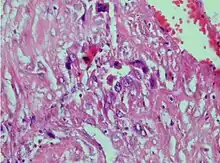

| Photomicrograph showing proliferating intermediate trophoblast with scarce cytotophoblastic and syncytiotrophoblastic elements | |

Placental site trophoblastic tumor is a form of gestational trophoblastic disease, which is thought to arise from intermediate trophoblast.[1]

A placental site trophoblastic tumor is a monophasic neoplasm of the implantation site intermediate trophoblast, and usually a benign lesion, which comprises less than 2% of all gestational trophoblastic proliferations. Preceding conditions include molar pregnancy (5%). Compared to choriocarcinoma or invasive mole, hemorrhage is less conspicuous and serum β-HCG level is low, making early diagnosis difficult.

Immunohistochemistry: Often stains with hPL, keratin, Mel-CAM, EGFR.